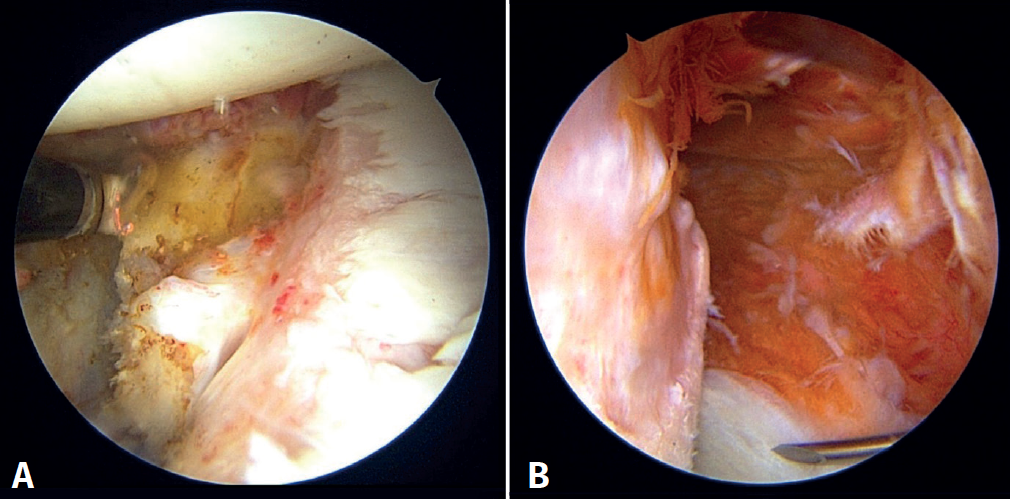

Third step: insertion and fixation of the graft. Capsulolabral reconstruction

We then start the bone block technique, rearranging the posterior portal so that a Wissinger-Rod® guide (Smith & Nephew) is rested on the glenoid surface and can be directed to the centre of the glenoid defect (Figures 5A and 5B). Next, we slide a hemi-cannulated guide or Glenoid Drill Guide® (Smith & Nephew) over it, the Wissinger-Rod® is removed, and the hook-ended articular arm of the guide is passed through it. This is positioned in the centre of the glenoid defect and is assembled onto the guide handle. The two cannulas that guide the perforations are also passed through the same handle in a posterior-anterior direction, making point incisions in the skin. The assembly is adjusted and cannulated sheaths, each mounted on a specific 2.8-mm drill, are inserted through the two cannulas; drilling is made until they protrude at the anterior surface of the glenoid neck, followed by withdrawal until they are flush with the glenoid neck. A nylon loop is passed through each sheath to retrieve the sutures.

Using the anterosuperior portal for vision, two anchorings are positioned for subsequent labral reconstruction. We use Suturefix Ultra® or Suturefix Curved® implants (Smith & Nephew), one at the midpoint of the lesion and another as distal as possible; we retrieve their extremities to the posterior portal.

Then, the bone block (lower part first) is guided through the metal cannula or directly through the extended anterior approach, followed by loop suture pulling and tightening, one by one. The bone block is positioned with the help of the hook guide. Once the position is considered to be satisfactory (Figure 5C), the implant sutures are passed through two buttons posteriorly using the suture retriever. Both are then advanced anteriorly (with a slip knot and a knot pusher) until they rest on the posterior surface of the glenoid neck (Figures 6A and 6B). Then, the sutures threaded to the posterior buttons are knotted using a Nice-type knot and tightened, as indicated by the technique, using a specific tensor up to 50 N. After doing this with both sutures, they are tightened again to 100 N and three safety half knots are added.